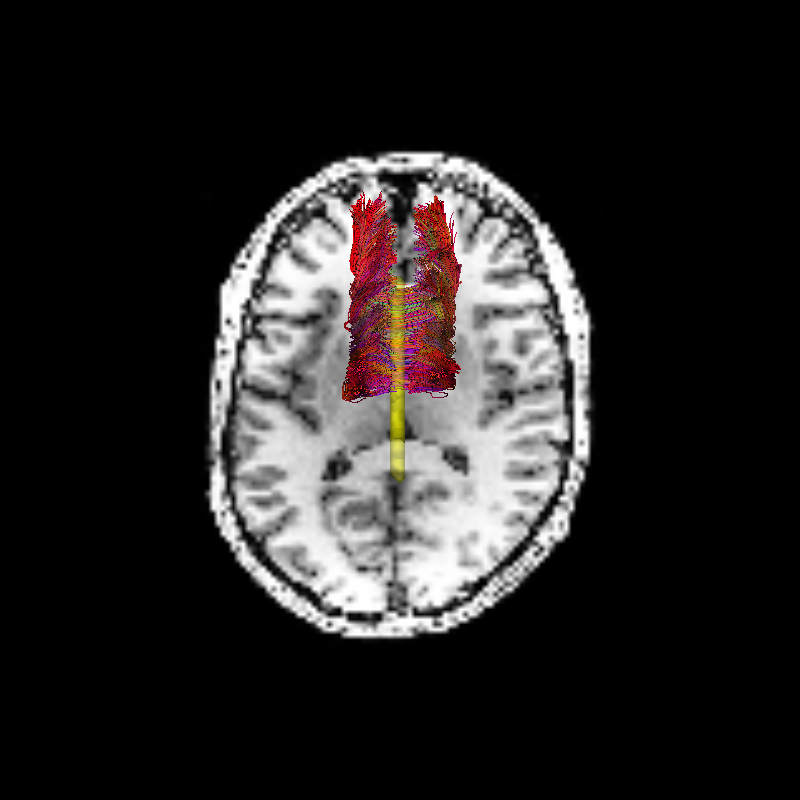

Let’s visualize the initial candidate group of streamlines in 3D, relative to the anatomical structure of this brain:

Candidate connectome before life optimization